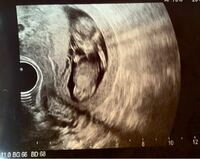

医師はどこを見て性別を判断しているのか? 医師はエコー写真のどこを見て、性別を判断しているのかというと、 赤ちゃんの足と足の間、股間部を見て主に男の子か女の子かを判断しています。 これは男女で最も違いのある部分なので、ここを確認すればすぐに結果がわかります。 お腹のなかの赤ちゃんの性別判定は、 超音波検査(エコー検査)で、赤ちゃんの性器を観察して行うのが基本です 。 男の子の場合は、両足の間にピーナッツのような睾丸の姿が映し出され 男の子の性別判定はいつから可能? 男の子の性別判定はいつから可能なのでしょうか? 男の子の性別判定は比較的早く、早くて15週・16週ごろからシンボルが見えてくる ようです! 私の場合、1人目の男の子が17週で性別ほぼ確定となりました。

妊娠26週目のエコー写真 お腹の赤ちゃんの性別が判明! 紛れもなく男の子のシンボルですよね! 先生が言う前に「先生、ついていますよね、これ」と私が言うほどに一瞬でわかりました。 実際、赤ちゃんの性別はいつわかるのでしょうか? そしてエコー写真で性別が分かる様になるのは、一体何週目くらいからなのでしょうか。 そんな赤ちゃんの性別に関する疑問を、詳しく解説していきます! 目次 赤ちゃんの性別はいつ決まる?